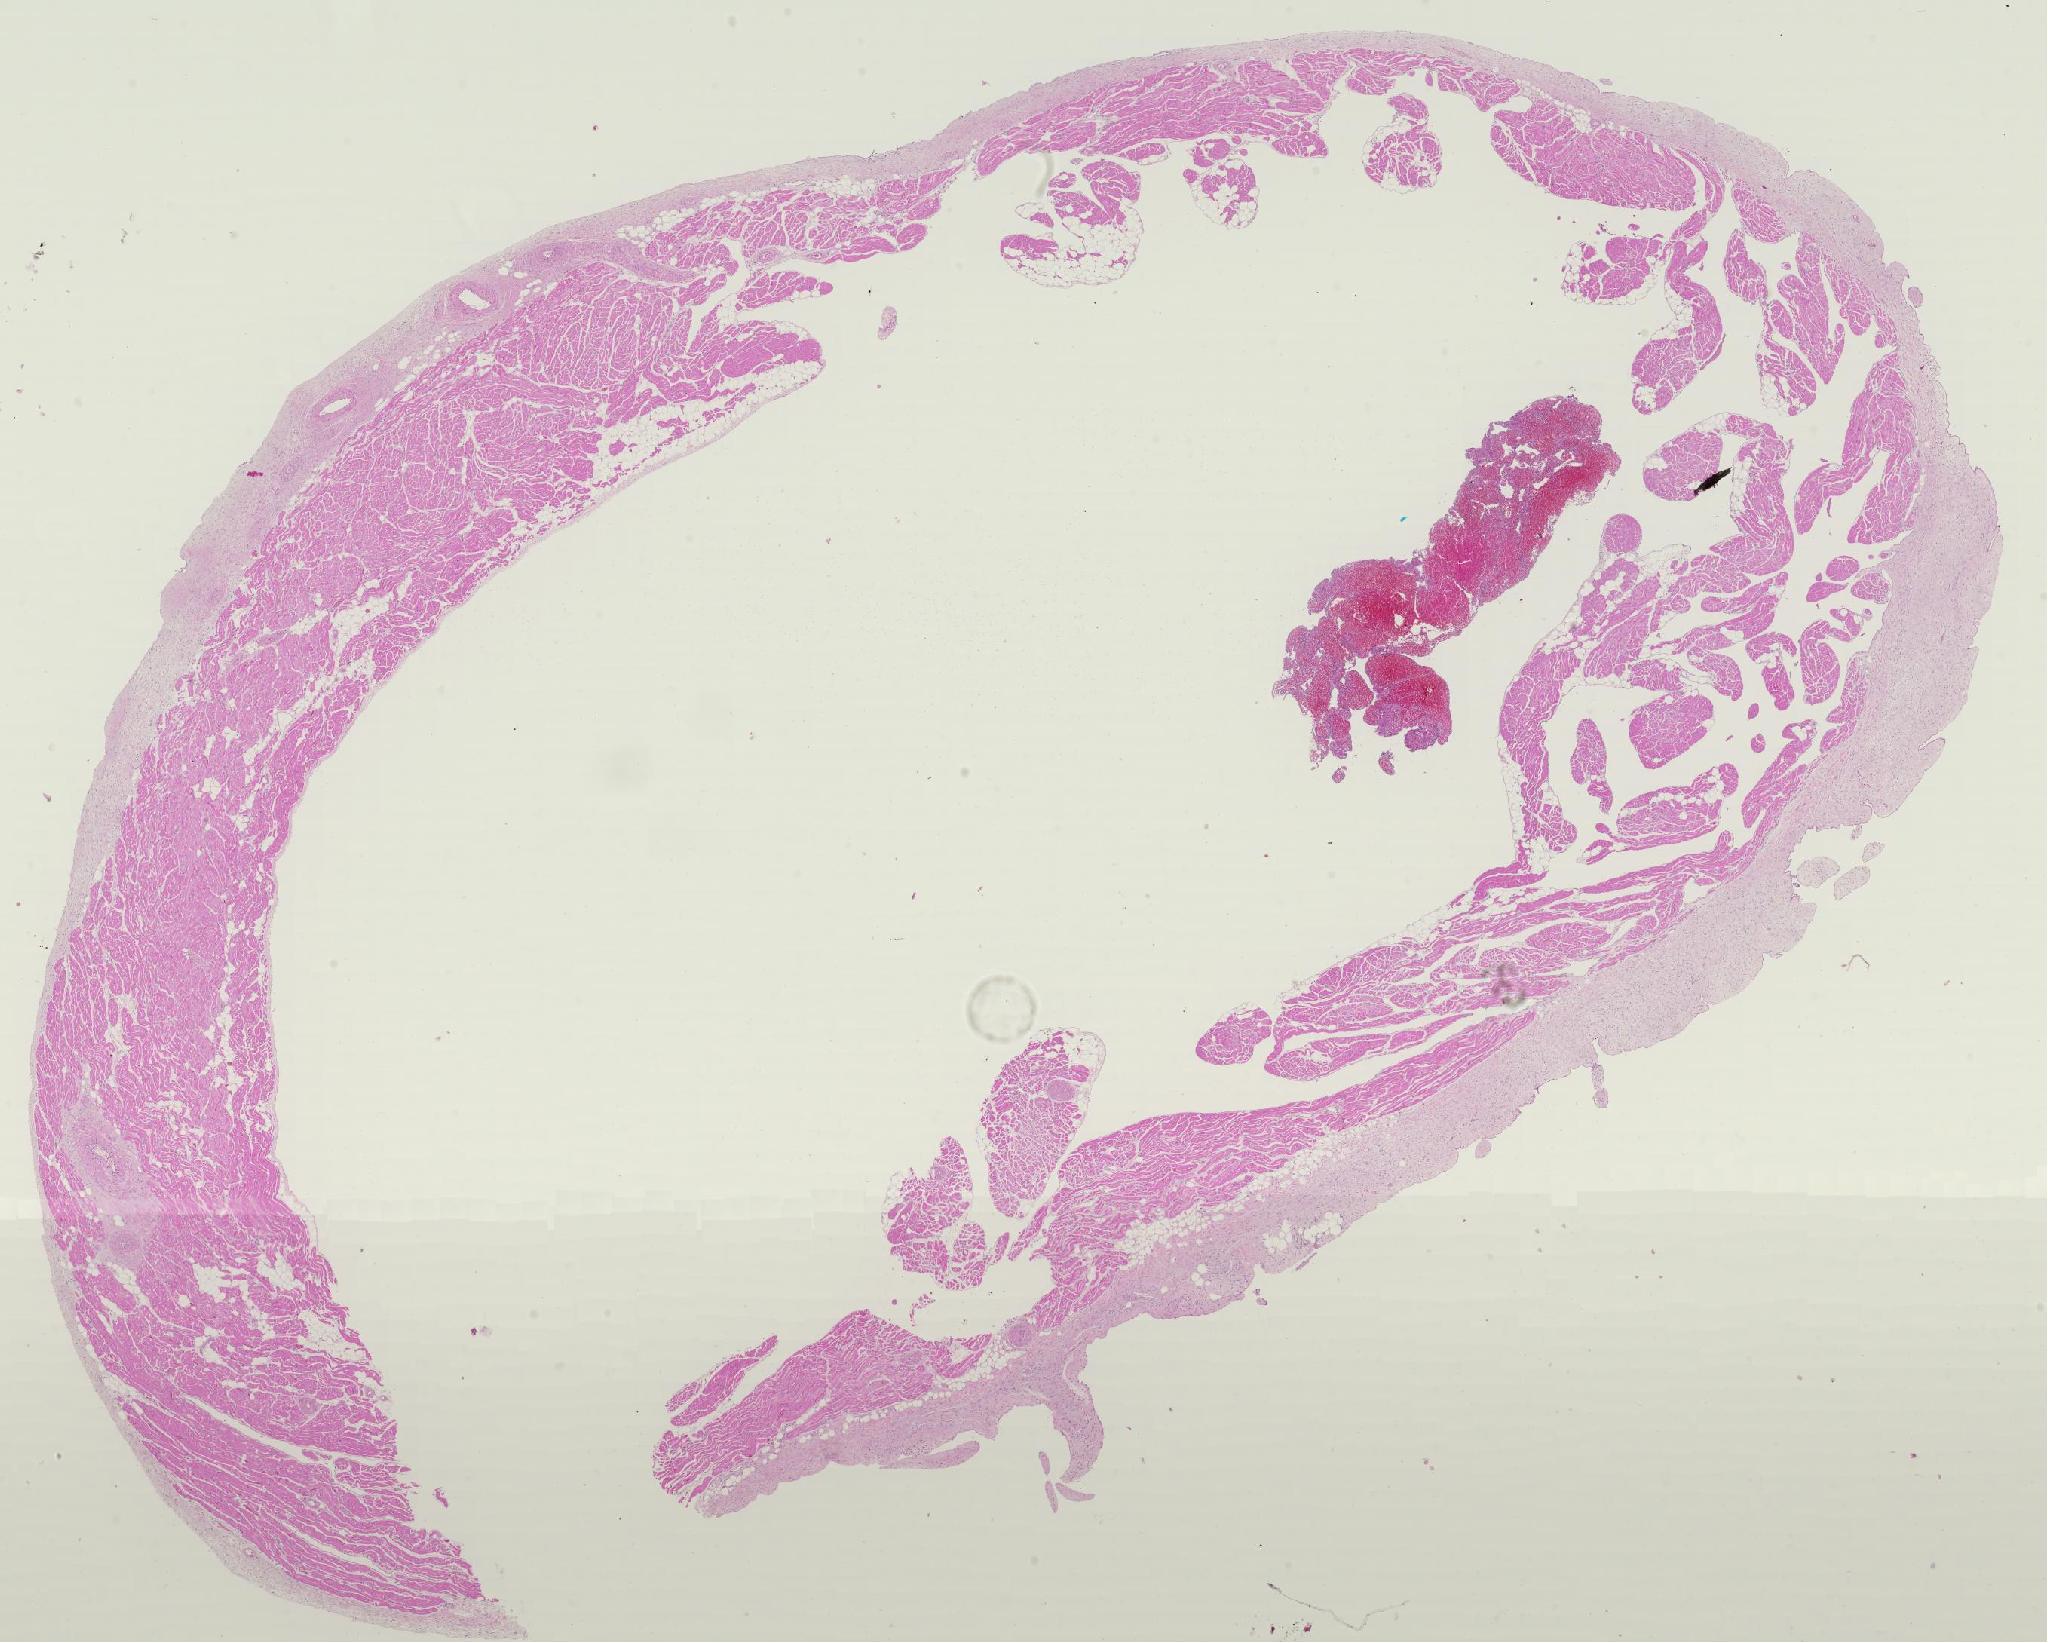

신장 / 기타 / 돼지